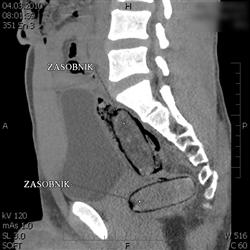

Olomoučtí celníci prováděli ve čtvrtek 4. března v nočních hodinách kontrolu mezinárodního rychlíku. Ten jel z Polska do Rakouska. Všimli si jednoho z cestujících, který vykazoval indicie naznačující pašování drogy. Pocházel z oblasti západní Afriky a trvalý pobyt měl v Evropské unii. Celníci provedli další kontroly za účelem detekce přítomnosti omamné psychotropní látky. Ty potvrdily výskyt drogy v těle. Následné CT vyšetření s jistotou prokázalo, že muž ukrývá v tělních dutinách čtyři kontejnery s neznámou látkou. Po vyloučení těchto předmětů z těla, za přítomnosti celníků, byl proveden drogový test a orientační vážení. Pasažér převážel v tělních dutinách 114 gramů kokainu. V lednu byl odhalen podobný případ, kdy cizinec přepravoval stejným způsobem 160 gramů kokainu.